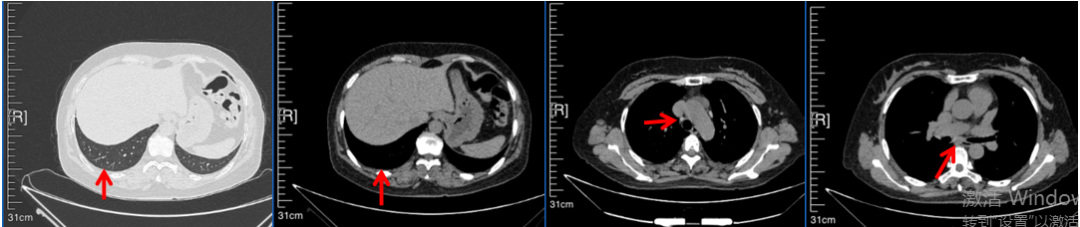

2016年1月复查CT提示支气管截断可见新发小结节,一线治疗采用培美曲塞+DDP方案化疗4周期(培美曲塞3.36,DDP 480mg)。化疗后复查胸部CT:右肺见不规则结节样影,最大层面大小约19mm*8mm,较前比较明显增大,疗效评估PD。2017.3-2017.4予单药多西他赛化疗3周期,疗效评估SD。2018年5月末复查CT提示结节较前增大,评效为PD,2018年6-10月予多西他赛+CBP化疗4周期,疗效评估SD。2022年5月患者出现活动后气短,复查胸部CT示右肺膨胀不良;右侧胸腔积液增多。胸腔积液包埋病理示符合肺腺癌细胞。行NGS基因检测:EML4:exon13-ALK:exon20融合。PD-L1(克隆号22C3)TPS<1%。

临床诊断:右肺上叶恶性肿瘤rT0N0M1a IVA期(第9版分期);恶性胸腔积液。

诊疗经过:2022年5月始口服克唑替尼3个月,出现肝功能异常(DILI 2级伴临床症状),改用恩沙替尼靶向治疗至今,目前评效为维持PR。恩沙替尼应用期间出现轻度肝功能异常(DILI 1级),对症处理后好转。截止目前PFS 33个月。

2018.07

2022.05

2022.08

2023.05

2024.12